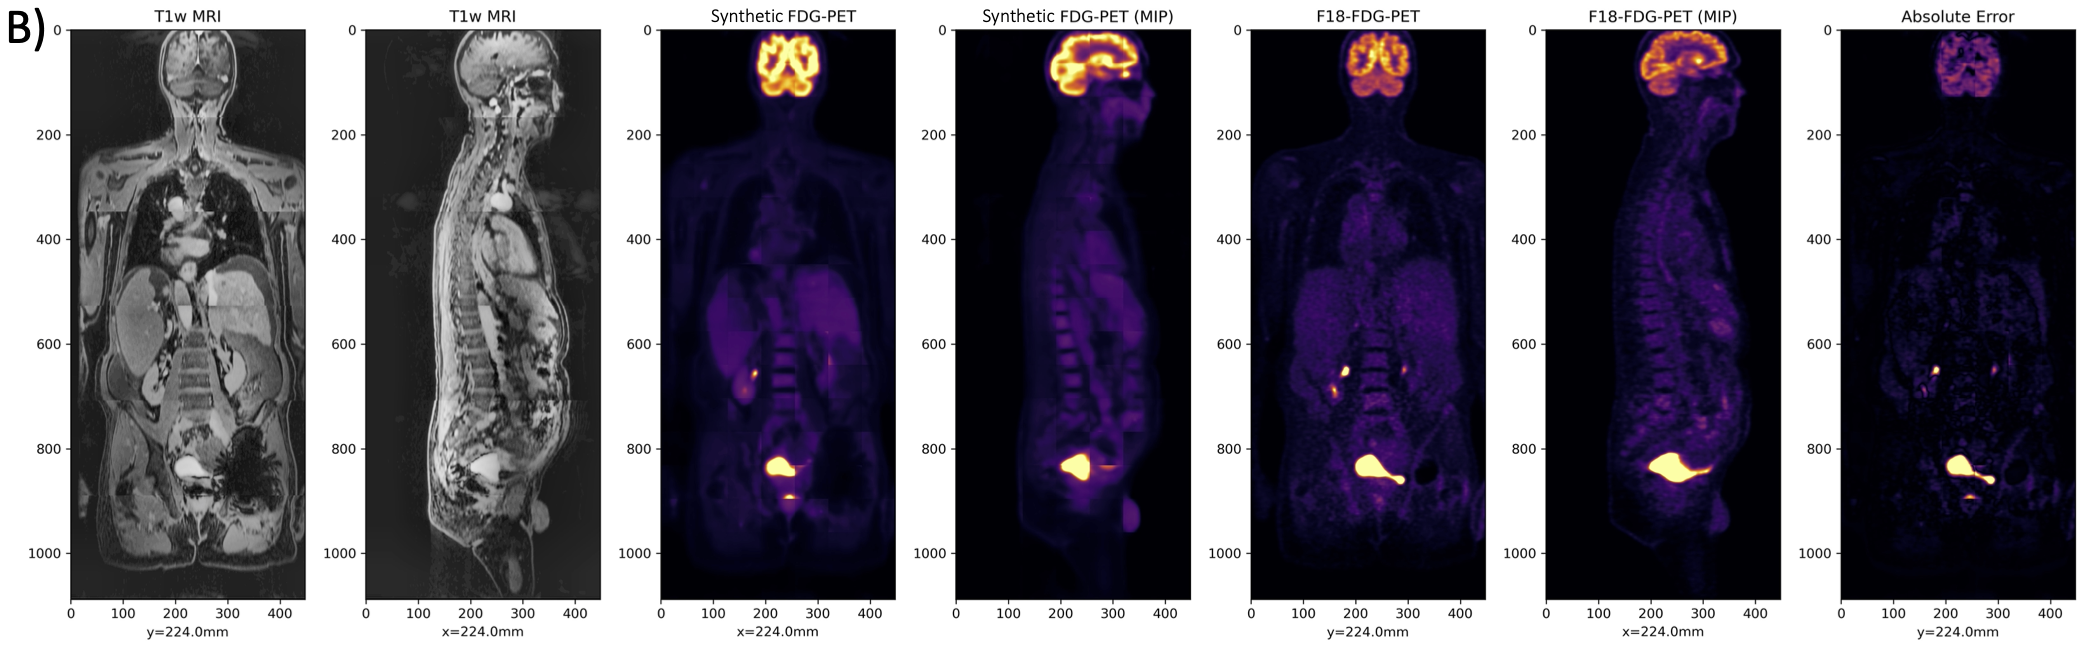

We find that prediction of synthetic FDG-PET, domain-translated from T1-weighted post-contrast MRI, works well despite the lack of salient tracer-specific or functional information in MRI (Fig. 3). Numerical results comparing the effect of different training objectives on test-set performance is shown in Table 1. Qualitative analysis reveals that physiologic uptake is predicted accurately and reconstructed seamlessly throughout the body without obvious spatial artifacts, except in regions where we expect variable uptake (e.g. heart, bladder). In the myocardium, for example, FDG-PET uptake depends on patient metabolism, which can vary across exams for even a single patient. Similarly, in the bladder PET uptake is often dependent on a patient’s water consumption and timing of voiding [34].